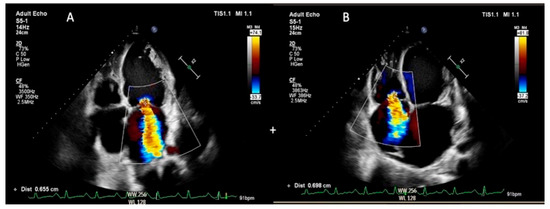

2.2. 2D Echocardiography Analysis

- Global regurgitation volume